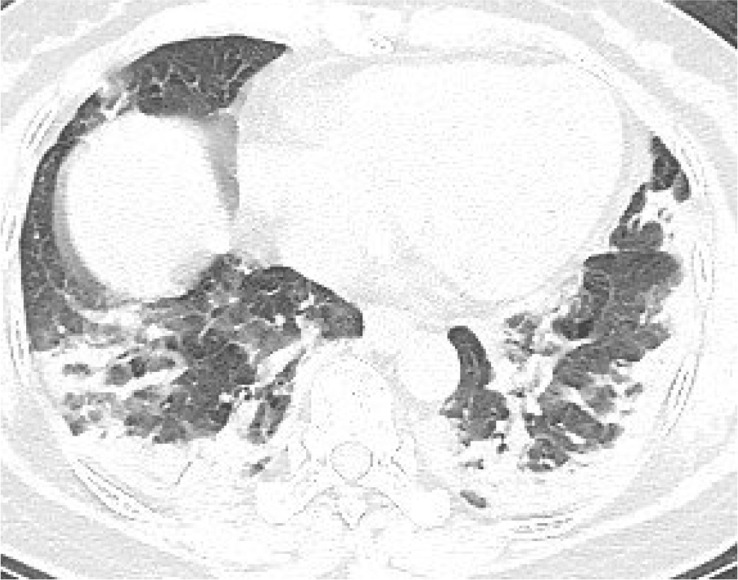

According to the guideline [9], CT examination is strongly recommended as a test for COVID-2019. According to the guidelines, the typical image of COVID-2019 presents multiple patchy ground glass opacity (GGO) along the subpleural and bronchovascular bundles in both lungs, separated by meshed or thickened lobular septa as crazy-paving pattern (54.2%) (Fig. 1, Fig. 2, Fig. 3, Fig. 4 ) and multiple patchy or large patchy consolidation in both lungs (Fig. 5 ), with thickening of interlobular septa, mainly in the middle and lower lobes (31.3%). It is consistent with the findings of Wang's [7] review of 138 cases (the CT findings of all cases involved both lungs), Huang's [1] review of 41 cases (all cases involved both lungs) and Song's [8] review of 51 cases (distribution: the lesions involved both lungs in 86% of patients, the lower lobe in 90% of patients, and the peripheral lung field in 86% of patients; density: 39% of the total number of lesions showed as GGO with reticular and/or interlobular septal thickening). Atypical images showed single lesion [10] (Fig. 6 ) and single or multiple consolidation nodules in the center of lobules, surrounded by ground glass opacities [9]. Both Song [8] and Pan [11] found that COVID-19 rarely caused mediastinal lymphadenopathy or pleural effusion.

Fig. 5.

51-year old female with intermittent fever (maximum temperature of 37.7 °C) for 1 week. Nucleic acid test: positive. Imaging examination: CT showed patchy consolidation along the subpleural in both lungs.

Fig. 6.

43-year old male with intermittent fever (maximum temperature of 39.5 °C) for 1 week. Nucleic acid test: positive. Imaging examination: CT showed a single mixed GGO nodule in the lower lobe of right lung.